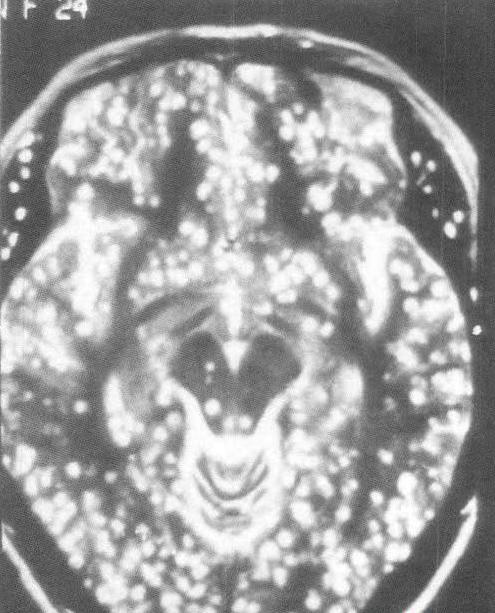

另位40多歲的張姓男子狀況更為嚴重,他因為頭部劇烈疼痛超過一個月而求診,起初只是靠服用止痛藥緩解,但後來發現即使加重劑量,藥效也愈來愈差。經過腦部掃描檢查後發現,他的腦中已經佈滿密密麻麻、難以計數的寄生蟲。醫療團隊追查病因後得知,張男長期食用僅經風乾處理、未經高溫烹煮的犛牛肉乾,導致蟲卵反覆進入體內,最終在腦部大量繁殖。